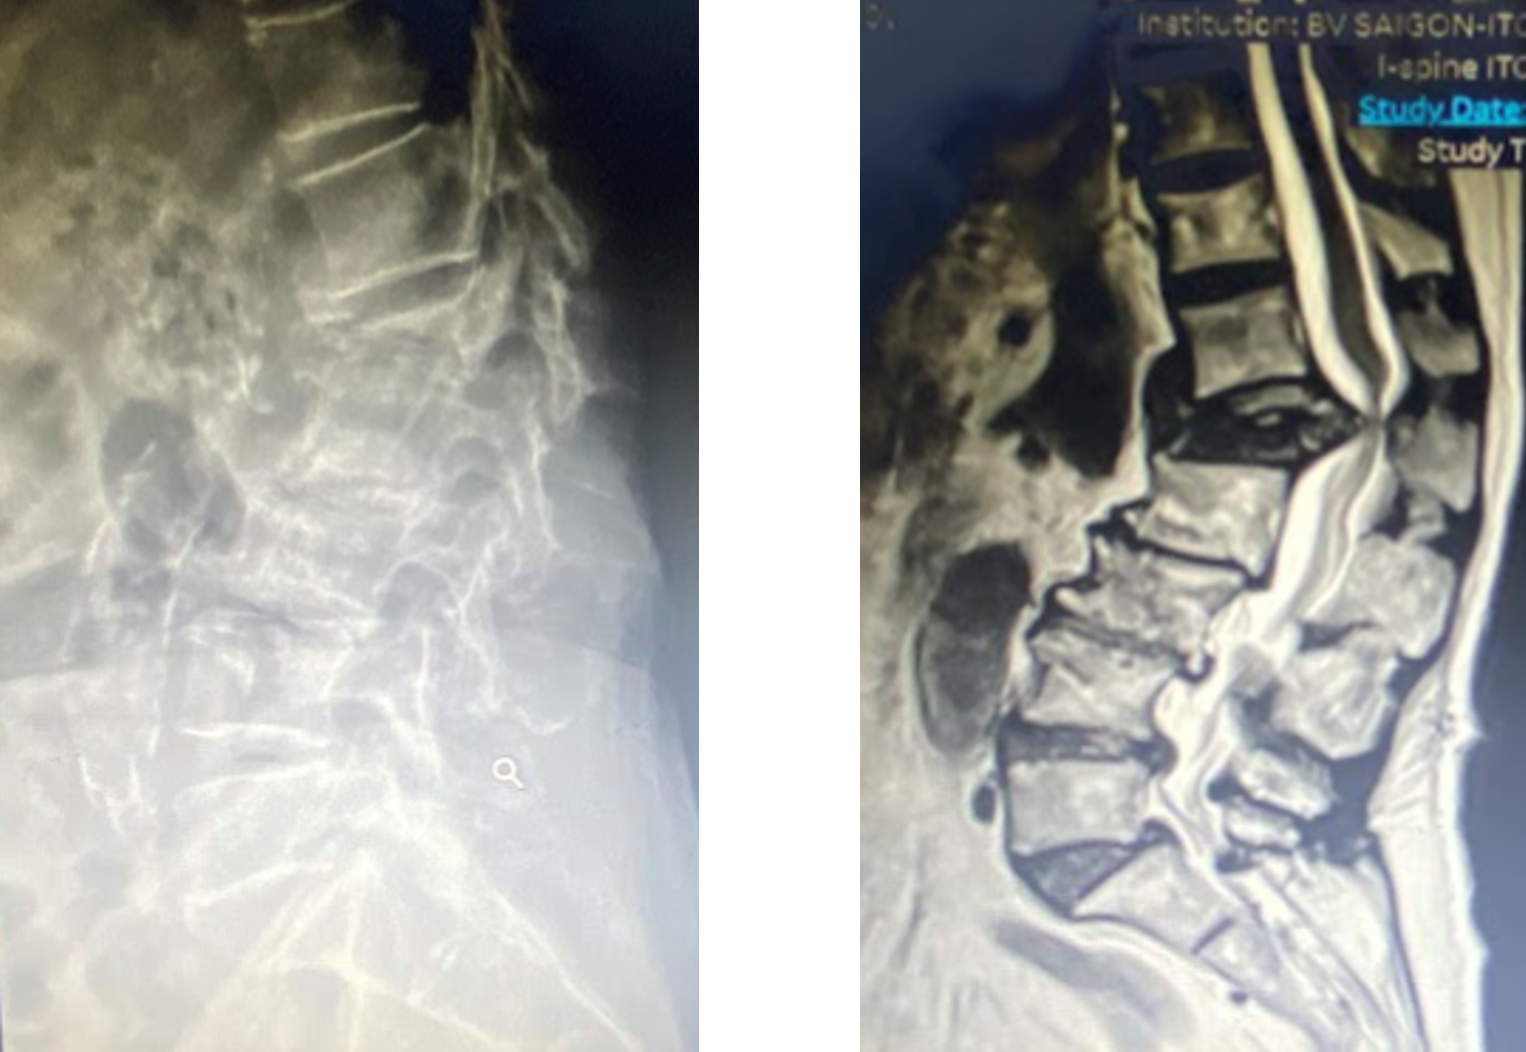

Tại đây, bệnh nhân được tiếp nhận trong tình trạng đau lưng kéo dài suốt ba tháng, tê bì hai chân và rối loạn tiêu tiểu mất kiểm soát. Qua thăm khám lâm sàng và thực hiện các cận lâm sàng cần thiết, BS.CKII Nguyễn Mạnh Tuấn - Khoa Chấn thương chỉnh hình, chẩn đoán cụ bị hẹp nặng ống sống, với các đặc điểm: gãy lún nặng đốt sống gây gù nặng, chèn ép ống sống đến 80%, tổn thương thần kinh do chèn ép tủy và mất vững cột trước cột sống nghiêm trọng.

Bệnh nhân còn có dấu hiệu của hội chứng chùm đuôi ngựa, bao gồm: rối loạn cơ vòng (mất kiểm soát tiêu tiểu, giảm trương lực cơ hậu môn), mất cảm giác vùng hậu môn và yếu vận động hai chi dưới. "Đây là tình trạng bắt buộc phải can thiệp phẫu thuật trong bệnh lý cột sống, nếu không sẽ dẫn đến liệt hai chân và mất chức năng tiêu tiểu vĩnh viễn", BS.CKII Nguyễn Mạnh Tuấn chia sẻ.